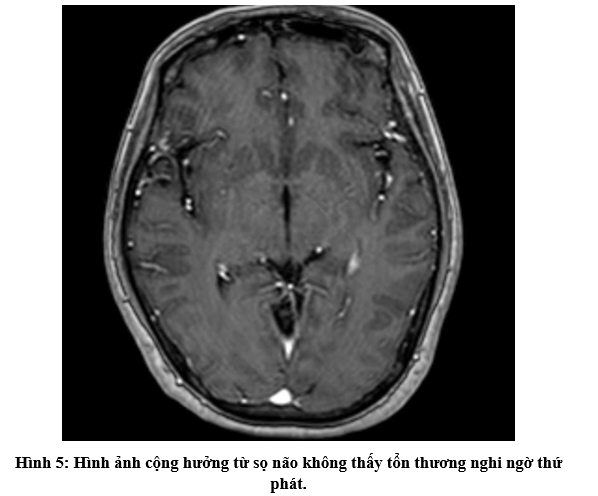

- Bệnh nhân không đau ngực, không khó thở, không sụt cân, không đau đầu